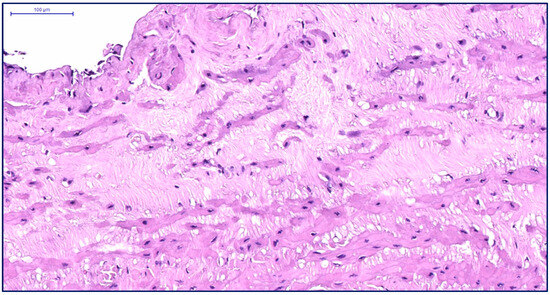

Effects of Two Decellularization Protocols on the Mechanical Behavior and Structural Properties of the Human Urethra

by Marcela Kuniakova, Zuzana Varchulova Novakova, Daniel Haspinger, Justyna Anna Niestrawska, Martin Klein, Paulina Galfiova, Jan Kovac, Michal Palkovic, Lubos Danisovic, Niels Hammer and Stanislav Ziaran

Int. J. Mol. Sci. 2024, 25(22), 12361; https://doi.org/10.3390/ijms252212361 - 18 Nov 2024

This study evaluates the effects of two decellularization protocols, enzyme-detergent (ED) and detergent-detergent (DD), on the structural and biomechanical properties of human urethral tissue. Urethral samples from 18 individuals were divided into ED (n = 7) and DD (n = 11) [...] Read more.

This study evaluates the effects of two decellularization protocols, enzyme-detergent (ED) and detergent-detergent (DD), on the structural and biomechanical properties of human urethral tissue. Urethral samples from 18 individuals were divided into ED (n = 7) and DD (n = 11) groups, with native samples (n = 3) serving as controls. Histological and ultrastructural analyses confirmed that both protocols effectively removed cellular content while preserving essential extracellular matrix (ECM) elements, such as collagen and elastic fibers. Immunohistochemical staining for collagen IV and fibronectin revealed no significant differences between decellularized and native tissues, indicating intact ECM structure. Biomechanical testing demonstrated that DD-treated tissues had significantly lower Cauchy stress (1494.8 ± 518.4 kPa) when compared to native tissues (2439.7 ± 578.7 kPa, p = 0.013), while ED-treated tissues were similar to both groups. Both decellularized groups exhibited reduced stretch at failure and elastic modulus compared to native tissues. Cytotoxicity assays using adipose-derived stem cells demonstrated no signs of toxicity in either protocol. Overall, both ED and DD protocols effectively preserved the urethral ECM structure and mechanical properties, making them suitable for potential use in tissue-engineered grafts and for biobanking purposes. Further research is needed to refine and optimize decellularization methods to improve scaffold recellularization and ensure clinical safety and efficacy. Full article